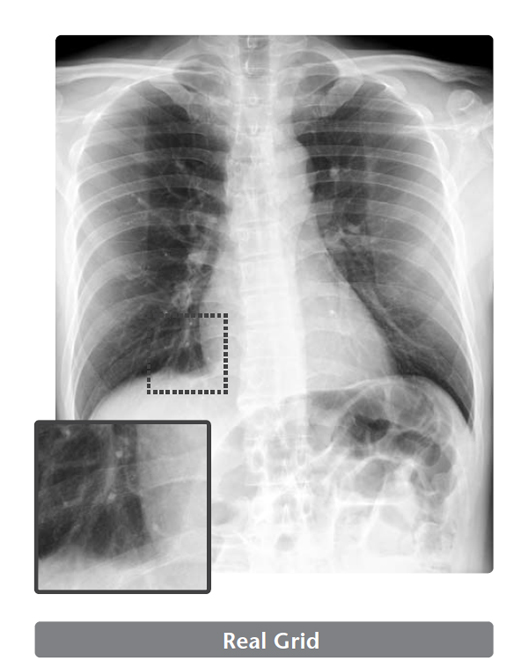

Virtual Grid

Image processing that remove the scatter X-rays from the digital radiography created without a physical grid.

Virtual Grid is an image processing software that corrects for the effects of scatter X-rays that otherwise reduce image contrast and clarity.

Without the need for physical grid, this software quickly predicts and then corrects for the effects of scatter X-rays, creating an improved image quality.

High quality images can be obtained under low dose conditions, thus reducing the amount of radiation does the patient receives

Virtual Grid selection

Virtual Grid allows setting of the grid ratio, number of grid lines and interspace material, and examinations using the appropriate grid conditions.

Just as for a physical grid, different Virtual Grid settings can be used, best suited for the different regions and exposure conditions.

Of course, as it is a virtually created grid, the grid type can be changed after an exposure.

Virtual Grid can be applied to all body parts. (Excluding breast imaging)